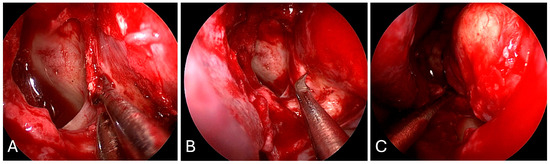

3.2.2. Illustrative Case

3.3.2. Illustrative Case